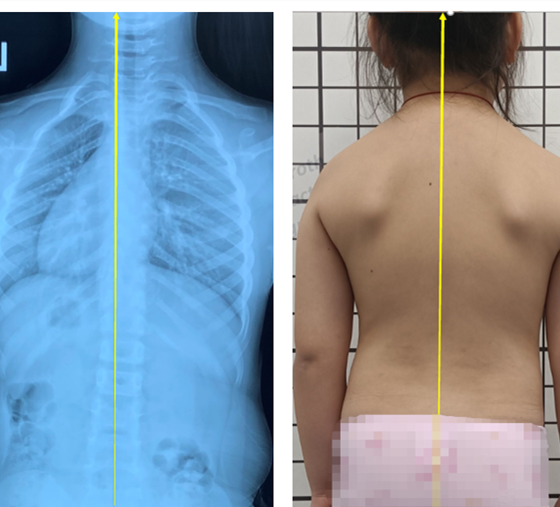

姿勢性脊柱側(cè)彎是由于不良姿勢導(dǎo)致的,通過拍片檢查,X線片顯示脊柱有偏移,cobb角度有的也超過10度,甚至有超過20度的。

姿勢性脊柱側(cè)彎又叫假性脊柱側(cè)彎,功能性脊柱側(cè)彎,是由于人體脊柱本身有側(cè)曲的功能,在拍片的一瞬間,采取了錯誤的站姿(或者平時的站姿就不好),導(dǎo)致片子上看到了側(cè)彎的存在。但測量剃刀背,度數(shù)在5度以內(nèi)(正常范圍),并沒有因椎體旋轉(zhuǎn)導(dǎo)致的肋骨變形,這樣的側(cè)彎,一般只需要觀察即可。

所以,姿勢性脊柱側(cè)彎只是脊柱在額狀面發(fā)生了偏移,并沒有在水平面發(fā)生旋轉(zhuǎn)畸形,還不是脊柱的三維畸形。這個時候就需要明確診斷,定期復(fù)查即可。不需要支具和矯形體操來干預(yù)。